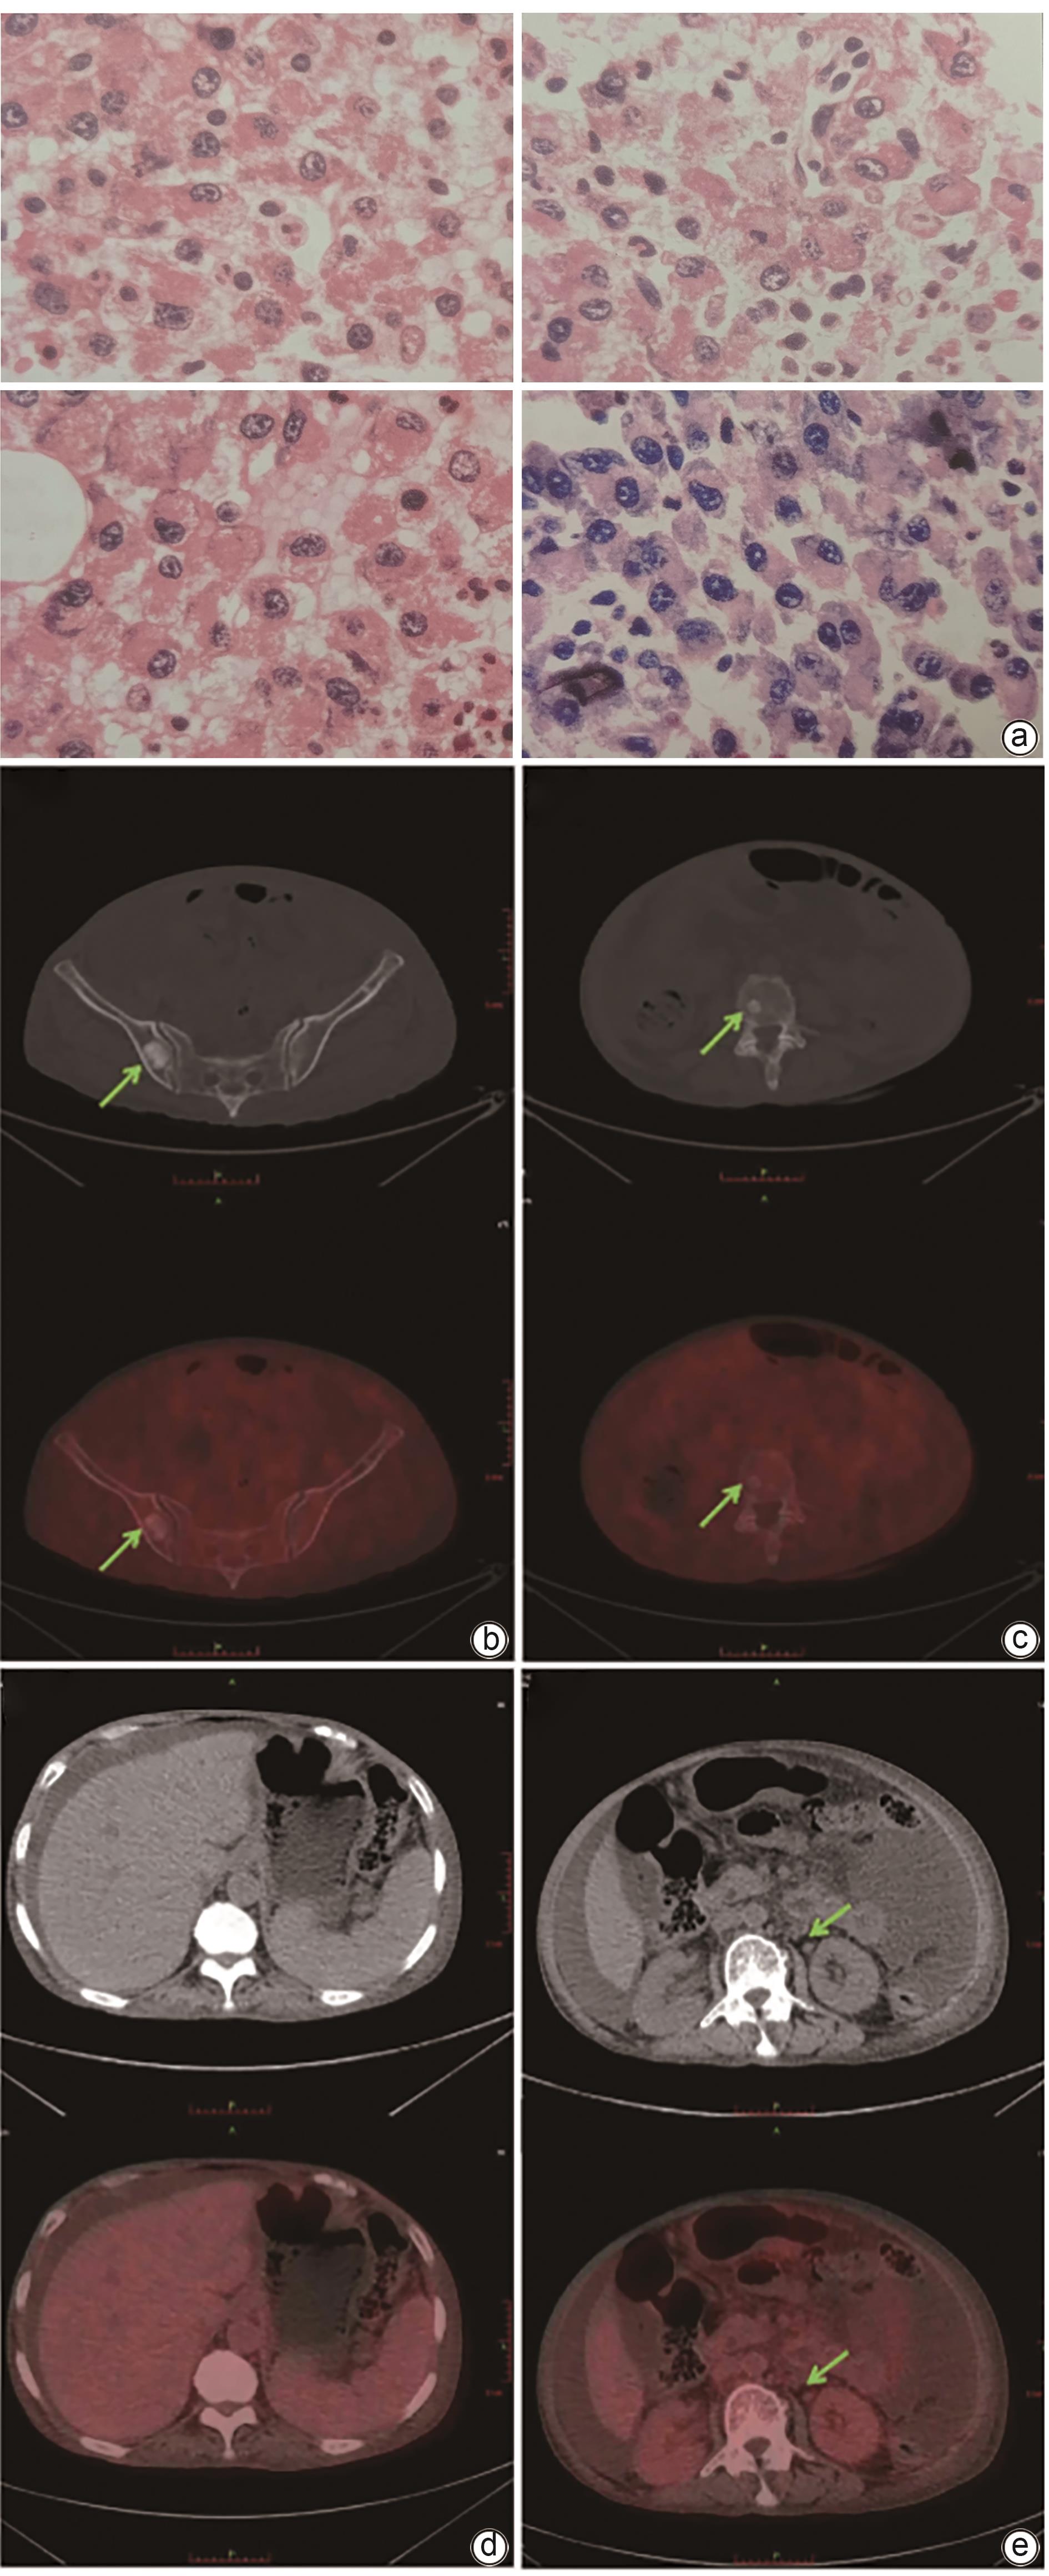

POEMS syndrome with hepatosplenomegaly as the initial manifestation: A report of two cases

Ye ZHANG, Wenqing WANG, Jing LI, Qianrong BAI, Jiayu LI, Yan CHENG, Miaomiao FANG, Nana GAO, Changxing HUANG

2025, 41(1): 127-132. DOI: 10.12449/JCH250119

Abstract(956) HTML (253) PDF (2190KB)(81)

Abstract:

POEMS syndrome is a rare condition associated with plasma cell disorders, and it often involves multiple systems and has diverse clinical manifestations. This article reports two cases of POEMS syndrome with hepatosplenomegaly as the initial manifestation. During the course of the disease, the patients presented with lower limb weakness, hepatosplenomegaly, lymph node enlargement, ascites, hypothyroidism, positive M protein, and skin hyperpigmentation, and 18F-FDG PET-CT imaging revealed bone lesions mainly characterized by osteolytic changes and plasma cell tumors. There was an increase in the serum level of vascular endothelial growth factor. The patients were finally diagnosed with POEMS syndrome, and the symptoms were relieved after immunomodulatory treatment.